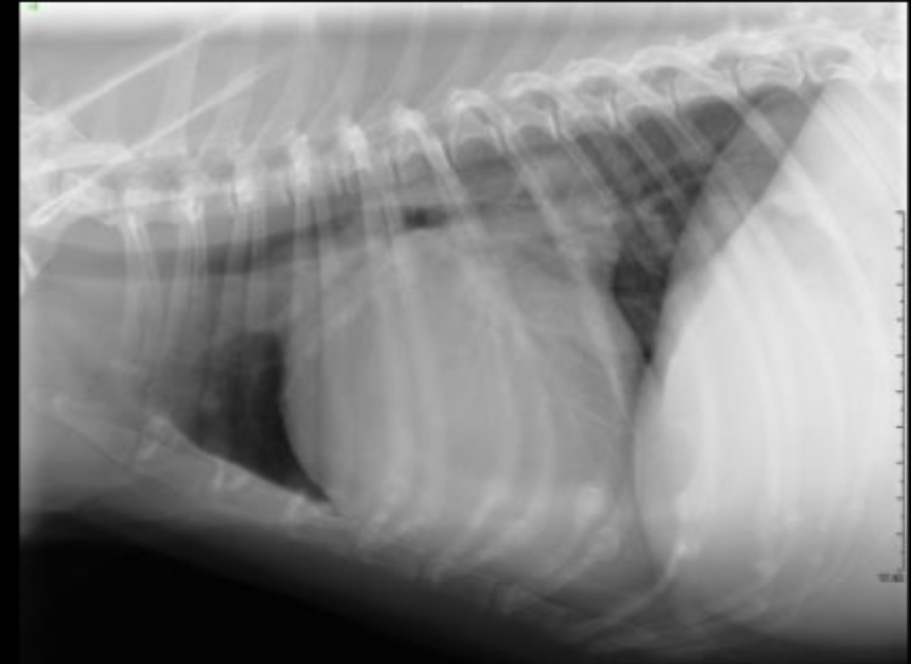

What part of the heart is enlarged on this lateral radiograph?

left ventricle

What radiographic changes can we see on a lateral or VD/DV view if there is left ventricular enlargement?

may appear radiographically normal

in severe enlargement, heart may elongate

dorsal displacement of the entire thoracic trachea (thoracic inlet to carina)